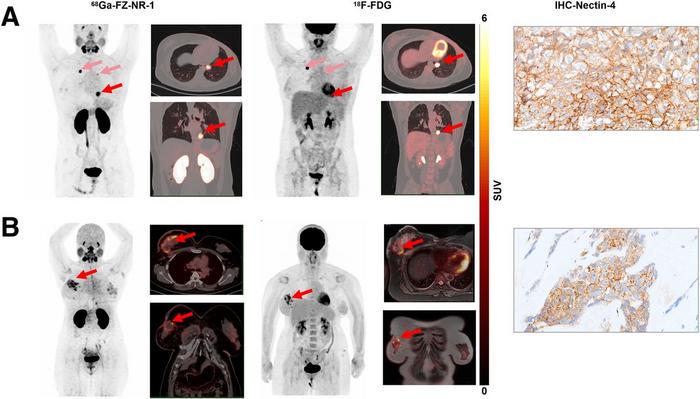

The application of 68Ga-FZ-NR-1 PET/CT imaging in these patients yielded remarkable outcomes, enabling the identification of tumors that were corroborated by conventional imaging techniques such as 18F-FDG PET/CT. This validation process underscored the accuracy of the novel radiotracer in pinpointing areas with elevated Nectin-4 expression. By comparing the findings from PET imaging with biopsy samples taken from the identified lesions, researchers could confirm the correlation between the radiotracer’s detection capabilities and the actual expression levels of the biomarker, thus reinforcing the scientific foundation of this innovative approach.

Image Credits: Created by Dr. Li Sun and Dr. Xiaoping Xu, Shanghai Cancer Center